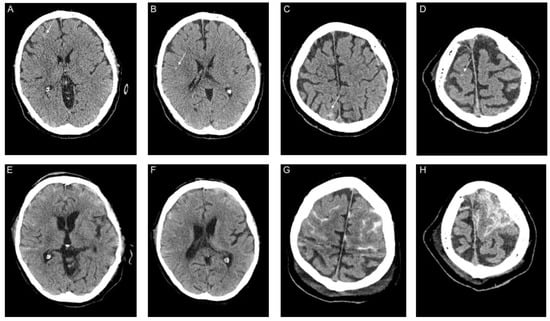

3.2. Imaging and Clinical Findings

| Parenchymal Hemorrhage (n = 6) | |

| Location | |

| • Lobar, n (%) | 4 (66.7) |

| • Deep, n (%) | 1 (16.7) |

| • Infratentorial, n (%) | 1 (16.7) |

| Ventricular extension, n (%) | 1 (16.7) |

| SAH extension, n (%) | 1 (0) |

| Subarachnoid Hemorrhage (n = 11) | |

| Primary SAH, n (%) | 9 (81.8) |

| • Aneurysmal, n (%) | - |

| • Cortical, n (%) | 9 (81.8) |

| • Bilateral, n (%) | 4 (36.4) |

| • Ventricular extension, n (%) | - |

| Secondary SAH, n (%) | 2 (18.2) |

| Intraventricular Hemorrhage (n = 3) | |

| Isolated IVH | |

| • Supratentorial, n (%) | 3 (100) |

| • Infratentorial, n (%) | - |

| • SAH extension, n (%) | - |

| Secondary IVH *1, n (%) | 1 (33.3) |

| Subdural Hemorrhage (n = 1) | |

| Convexity, n (%) | 1 (100) |

| Bilateral, n (%) | - |

| SAH extension, n (%) | 1 (100) |